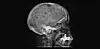

Mange mennesker med beinmargskreft ender ofte opp med hullete skjelett. Dette er svært smertefullt å leve med. På dette fotoet vises hull i kraniet.(Foto: Dr. Jennie Roberts, Radiopaedia.org)

Mange mennesker med beinmargskreft ender derfor ofte opp med hullete skjelett. Dette er svært smertefullt å leve med. Mange kan oppleve at ryggraden kollapser eller at bein brekker bare av å snu seg i senga.